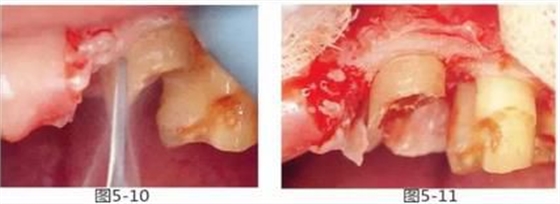

圖5-10,11

使用鎢鋼車針削除牙根表面附近的牙槽骨和纖維。之后,再使用牙骨鑿盡可能平滑地將治療部位轉(zhuǎn)移到牙槽骨和牙齒的移行處。